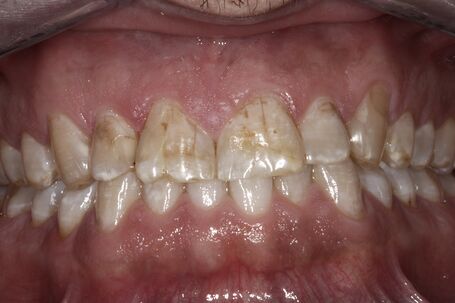

vor der Behandlung ohne Veneers

vor der Behandlung